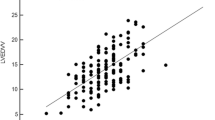

Interobserver agreement was substantial for IVCCI (CCC = 0.97), dIVCmax-to-IVCCI (CCC = 0.961), E/Em ratio (CCC = 0.962) and SVI (CCC = 0.953) and moderate for FAC (CCC = 0.904). Interobserver agreement was furthered analyzed by Bland-Altman plots (Fig. 5).

Interobserver agreement of various echocardiographic variables. IVCCI = inferior vena cava collapsibility index, dIVCmax = maximum diameter of IVC at expiration, FAC = fractional area change, SVI = stroke volume index, E = peak velocity flow in early diastole, Em = the average of peak velocities in early diastole of lateral and septal mitral annulus